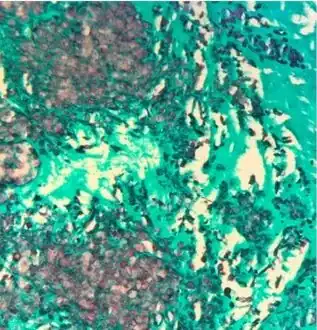

Gomori methenamine silver stain highlights numerous budding yeast and occasional pseudohyphal forms in mitral valve corresponding to C. lusitaniae recovered from culture -